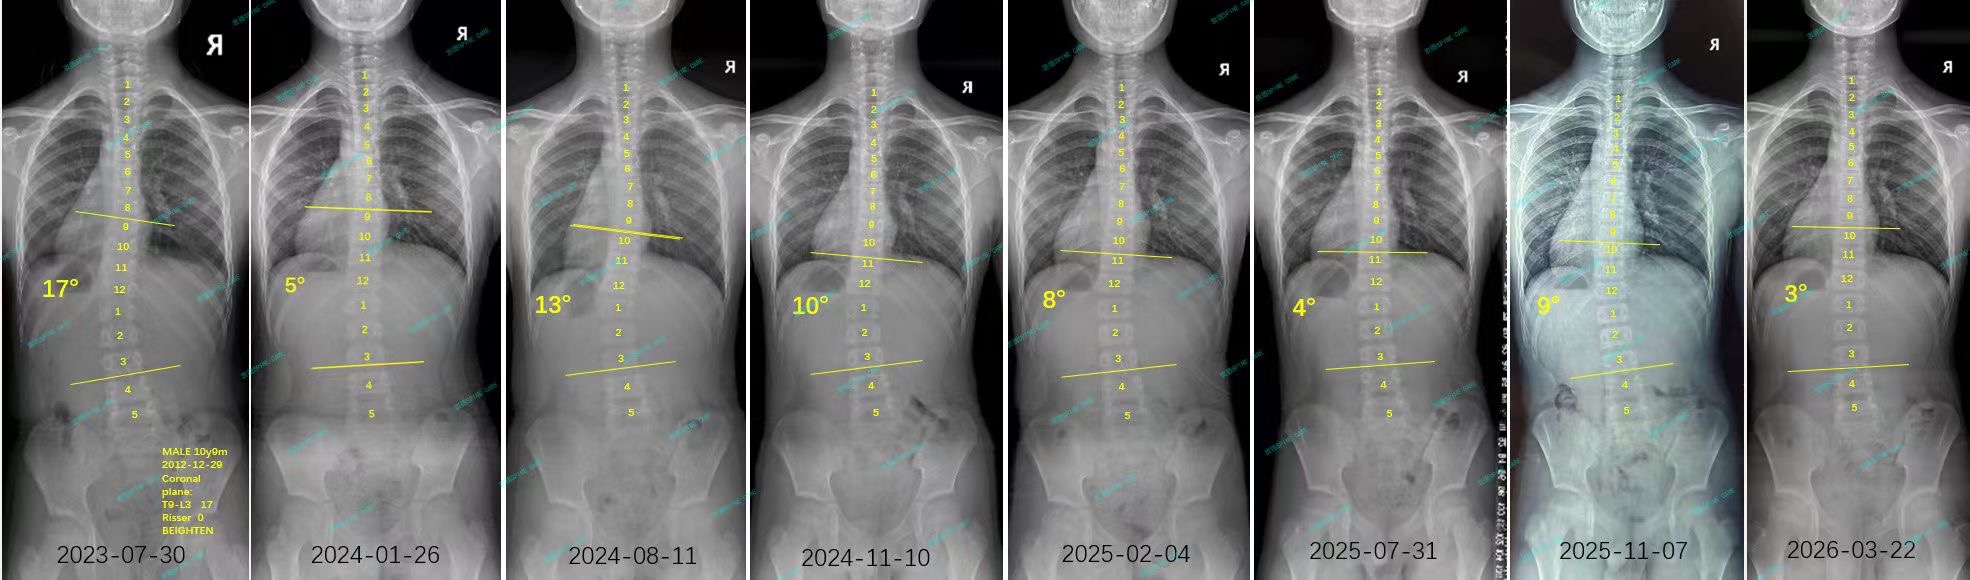

我是小俊,从17度到3度,这是我的脊柱侧弯修炼手册

案例主人:小俊 发现侧弯年龄:12岁 侧弯情况:Cobb角度17度

这一年我长高了10cm,训练也让我的体态看起来挺拔了许多,现在我整个人都笔笔直的,努力也没有白费。现在我的角度已经降到了3度,体态也明显改善了。杨医生说,康复就像爬山,偶尔会滑倒,但只要方向对了,总能登顶。而对我来说,TFboys的歌就是一路上的背景音乐,让我每一步都走得更有力量。感谢杨医生和他的团队的专业指导,没有杨医生团队的专业指导,我不知道我还要在脊柱侧弯康复中走多少弯路。

As expected, all my hard work paid off: the angle has now decreased to 3 degrees, and my posture has significantly improved.Dr. Yang explained that rehabilitation is akin to climbing a mountain; occasionally, you might slip, but as long as you stay on the right path, you will eventually reach the summit. For me, the songs by TFBoys have served as background music, giving me the strength to take each step forward. I am deeply grateful to Dr. Yang and his team for their professional guidance; without their expertise, I fear I would have taken many unnecessary detours in my journey toward recovery from scoliosis.